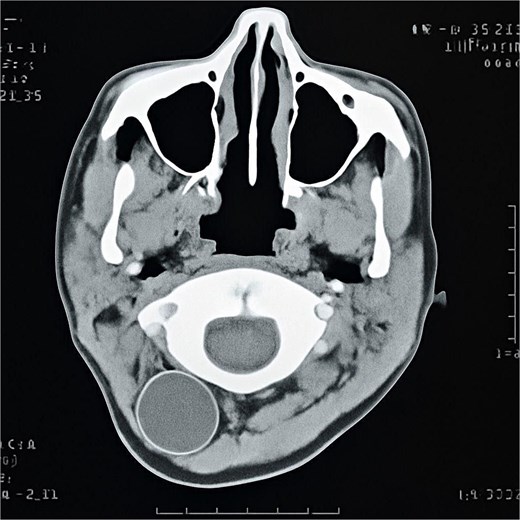

A 13-year-old female patient from the countryside went to the clinic, presenting with an occipitocervical mass. The patient possessed no noteworthy medical history aside from a surgical history of appendectomy. A physical examination indicated a tender and painless occipitocervical mass. Ultrasound identified a 21 × 34 mm fluid-filled cyst. Computed tomography (CT) excluded connection with the meninges or spinal column (Fig. 1). Serologic tests were negative. No additional cysts were identified elsewhere in the body. All laboratory values were within normal limits. The preliminary differential diagnosis included a thyroid cyst, primary thyroid lymphoma, or lymphatic malformations. The patient underwent surgical excision of the cyst without complications and was sent to pathology. Histopathology showed a laminated membrane and inner germinal layer with daughter cysts, consistent with E. granulosus cyst (Figs 2 and 3). Albendazole was administered postoperatively at 400 mg twice daily for 4 months. Throughout this period, liver function tests were monitored biweekly, with results remaining within normal limits. During the follow-up period, there was no recurrence or new cyst formation.